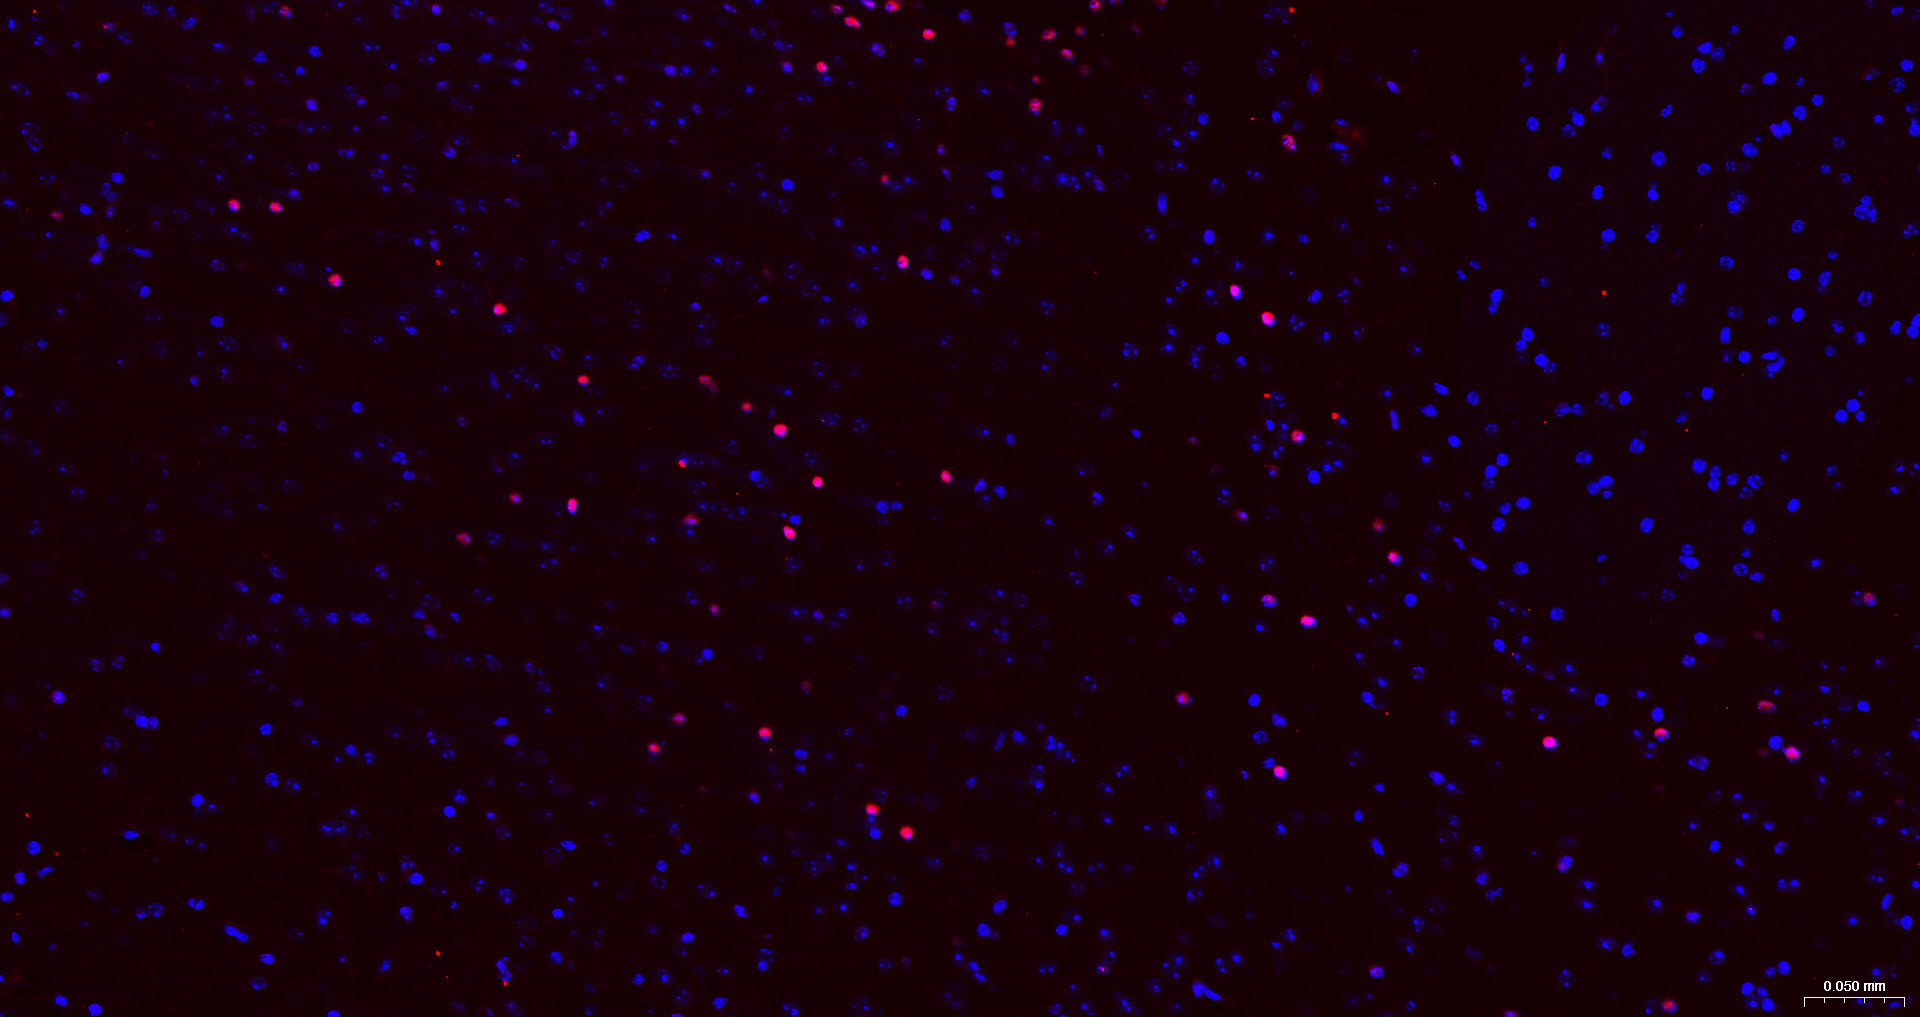

Paraformaldehyde-fixed, paraffin embedded Human Colon Cancer; Antigen retrieval by boiling in sodium citrate buffer (pH6.0) for 15 min; The section was incubated with SOX9 Monoclonal Antibody, Unconjugated (bsm-63031R) at 1:200 overnight at 4°C. Followed by conjugated Goat Anti-Rabbit IgG antibody (Red, bs-0295G-BF594), DAPI (blue, C02-04002) was used to stain the cell nuclei.